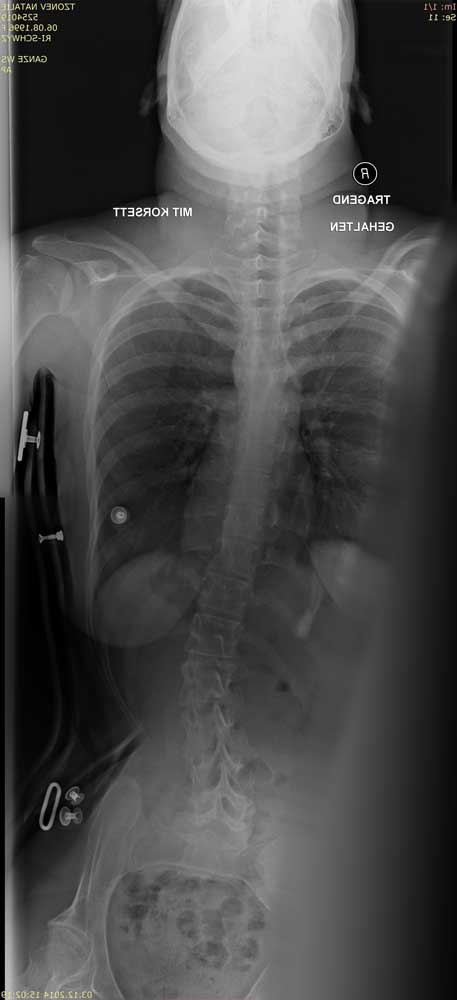

Standardisierte anterior-posteriore (a.-p.) Röntgenbilder wurden retrospektiv ausgewertet. Die Aufnahmen wurden bei allen Patienten in sitzender Position durchgeführt. Bei 3 Patienten wurden Röntgenbilder in stehender Position angefertigt. In liegender Position angefertigte Röntgenbilder waren nicht zulässig, da das maximale Ausmaß der Verkrümmung in dieser Position durch die fehlende Schwerkraft nicht sichtbar ist. Anhand der a.-p. Röntgenbilder wurden der Apex sowie die lumbalen und thorakalen Cobb-Winkel berechnet. Alle Winkel wurden mittels „Centricity Dicom Viewer V3.1“ gemessen. Bei demselben Krankenhaustermin wurden zwei Röntgenbilder angefertigt: eine erste Röntgenaufnahme (T1) mit Doppelschalenkorsett und nach 5 Minuten (T0) ein zweites Röntgenbild ohne Korsett. Dies war allerdings nur bei Patienten mit korrekter Anpassung des Doppelschalenkorsetts möglich. Bei den anderen Patienten betrug die Zeitspanne zwischen T1 und T0 nicht mehr als 3 Monate aufgrund notwendiger Anpassungen des Doppelschalenkorsetts durch den Orthopädietechniker. Der Grad der Korrektur des Cobb-Winkels im Bereich der Lenden- und Brustwirbelsäule wurde in Prozent des Messergebnisses ohne Korsett bei T0 ausgedrückt (Abb. 1 u. 2).

Insgesamt wurden 40 der 50 (80 %) Röntgenbilder am selben Tag aufgenommen (T1 und T0). Zehn Röntgenbilder (20 %; n = 5 Patienten) für T0 und T1 wurden nicht am selben Tag, sondern innerhalb eines Zeitraums von weniger als 3 Monaten angefertigt. Während dieses Zeitraums mussten Anpassungen am Doppelschalenkorsett vorgenommen werden. Alle Doppelschalenkorsetts wurden 4, 8 und 12 Wochen nach der ersten Versorgung durch die Orthopädietechniker klinisch geprüft. Im Bereich der Lendenwirbelsäule wurde eine mittlere (± Standardabweichung) Verkrümmung von 45,7° (19,2°) gemessen. Die mittlere innerhalb eines Zeitraums von 3 Monaten erreichte Korrektur bei Verwendung eines Doppelschalenkorsetts betrug 20,9° (13,1°; p < 0,05). Dies stellt eine Verbesserung um 49,9 % dar. Im Bereich der Brustwirbelsäule wurde eine mittlere Skoliose von 40,5° (17,8°) berechnet. Diese wurde im Doppelschalenkorsett durchschnittlich um 13,8° (10,3°; p < 0,05) korrigiert. Dies stellt eine Verbesserung um 33,1 % dar. Die Tabellen 2 und 3 enthalten eine Auflistung der Korrekturen für alle 25 Patienten im Bereich der Lendenwirbelsäule (Tab. 2) und der Brustwirbelsäule (Tab. 3).

Die Abbildungen 3 und 4 zeigen die klinischen und radiologischen Befunde für eine 18-jährige Frau (Fall 17). In Abbildung 3 sind die klinischen Fotos ohne und mit Doppelschalenkorsett zu sehen. Abbildung 4 zeigt die Röntgenbilder dieser Patientin ohne (a) und mit (b) Doppelschalenkorsett.